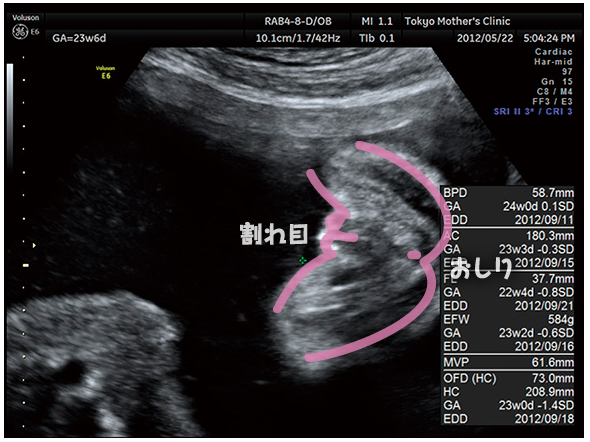

妊娠23週3日 23w3d の超音波 エコー 写真

妊娠22週 エコー写真で見る胎児の大きさ 胎動 22週の壁とは 妊娠中期 All About